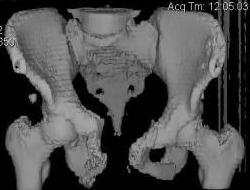

Уважаемые коллеги! Девушка 18л сросшиеся переломы лонных, седалищных костей с обеих сторон, перелом крестца справа,перелом костей голени справа (зио), 3 мес после травмы, АВФ снят с таза.

Патологической подвижности нет. Стоит самостоятельно, ходит с костылями, поскольку 3 месяца практически не ходила. Беспокоит выступание лонной кости в области лобка, хотя объективно грубого косметического дефекта нет. На кт разворот лонной кости в сагиттальную плоскость. Вопрос: стоит ли добиватьсяполной репозиции или же достаточно произвести остеотомию верхушки выступающего отломка?

Предварительный диагноз- посттравматическая вертикальная нестабильная деформация таза II степени, неправильно срастающийся перелом боковой

массы крестца справа, правой лонной и седалищной костей, застарелый разрыв лонного сочленения.

Для уточнения диагноза ниеобходимы обзорные рентгенограммы таза (прямая и inlet), Кт срезы на уровне переломов для определения степени сращения и решения вопроса о методе оперативного восстановления анатомии (делать ли остеотомию, низводить ли задние отделы), ни о какой "остеотомии выступающих отломков" тем более у девочки 18 лет речи быть не может.